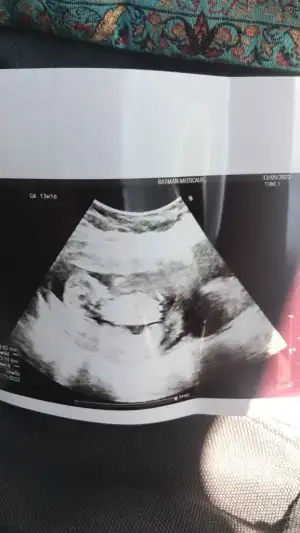

Hala kız gibi duruyor13 haftalık göstermedi bugün kendinidaha önce kız dedin hadi bakalım :)

karından 13 haftalık burdaSelam Kızlarbir çok kişi gruplardan beni bilir. Yine yetiştim imdatlara

başka foto yok mu burda göbekten aşağı görünmüyor, ayrıca renkli değil de siyah beyaz varsa? 7-8 haftalık hali de varsa onu da yüklerseniz yorum yapabilirimkarından 13 haftalık burda![]()